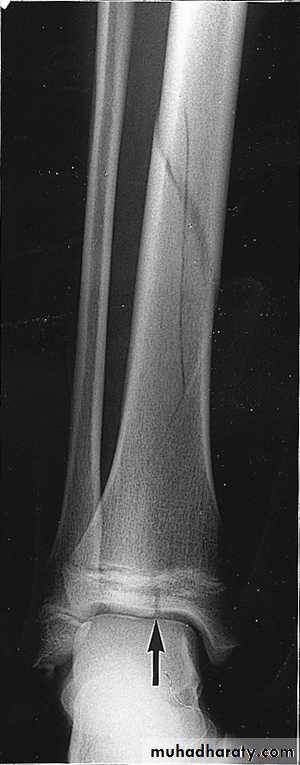

• Stress or fatigue-repetitive stress(athletes, dancers, army recruits)

4- Bone scan : like in stress fractureHow fracture heals ?